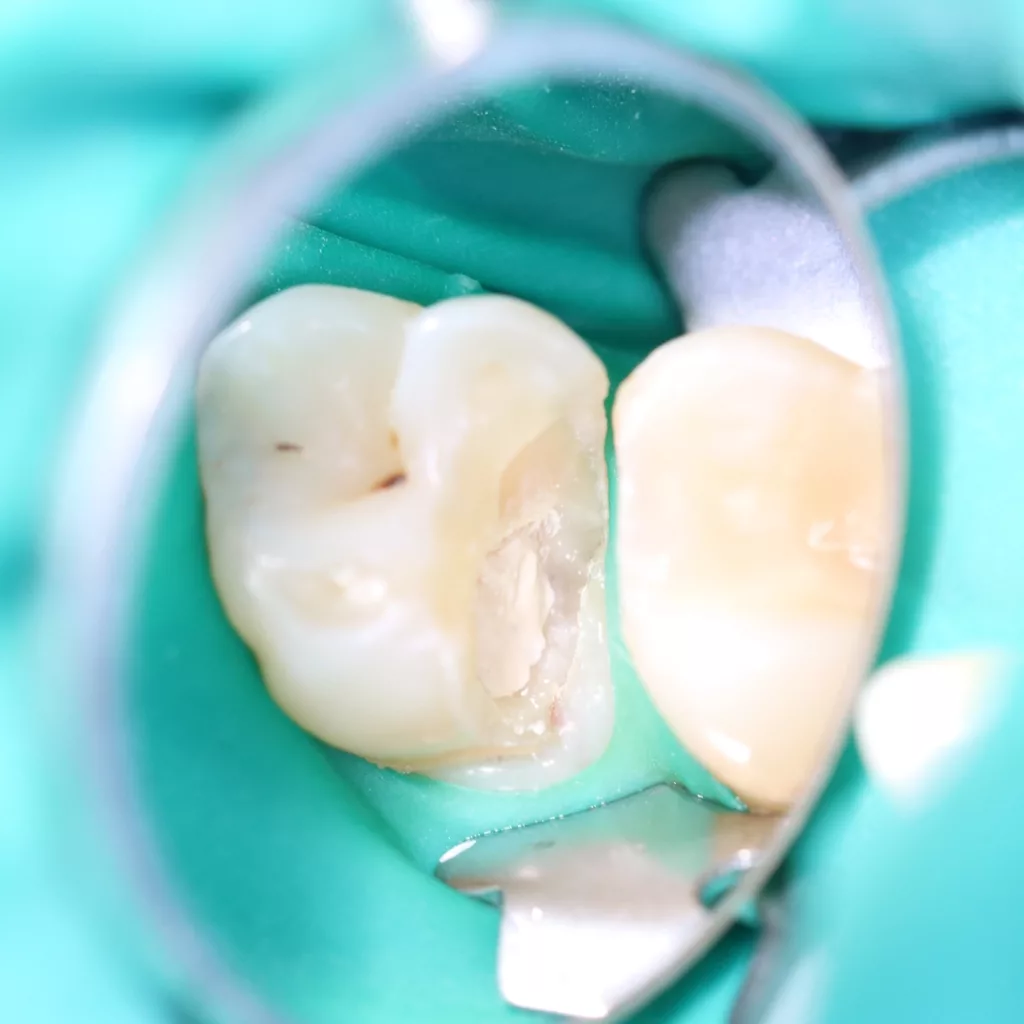

Wird eine profunde kariöse Läsion behandelt, empfiehlt sich folgendes Vorgehen [5]: Zunächst sollte in einem ersten Schritt ein Kofferdam appliziert werden, um eine möglichst keimfreie Arbeitsweise zu gewährleisten. Nach Präparation einer Zugangskavität, wenn dies notwendig ist, erfolgt die Kariesexkavation mittels Rosenbohrern oder Handexkavatoren. Wird in pulpanahen Arealen eine Eröffnung der Pulpa erwartet, sollte das Instrument gewechselt und ein sauberer Rosenbohrer genutzt werden. Tritt nach vollständiger Kariesexkavation keine Eröffnung der Pulpa ein, ist aber von einer dünnen Restdentindicke von etwa 300 µm auszugehen, oftmals erkenntlich durch eine zartrosa hindurchschimmernde Pulpa, sollte nach Kavitätentoilette mittels Natriumhypochlorit (NaOCl) 3% eine indirekte Überkappung mit einem hydraulischen Kalziumsilikatzement erfolgen [5]. NaOCl dient dazu, Bakterien und Toxine zu neutralisieren und das Dentin zu desinfizieren. Die Unterfüllung aus Kalziumsilikatzement soll auch desinfizierend wirken, das Pulpagewebe zur Heilung anregen und vor möglicherweise durch das Dentin penetrierenden Monomeren aus dem Dentinadhäsivsystem schützen [5], da diese die regelrechte Funktion der Odontoblasten beeinträchtigen können [9,40]. Im Anschluss muss eine direkte, dentinadhäsive Restauration zur Versorgung der Kavität platziert werden [5]. Die Abbildungen 1 bis 14 illustrieren das Vorgehen bei der Behandlung einer profunden kariösen Läsion mit indirekter Überkappung der Pulpa.